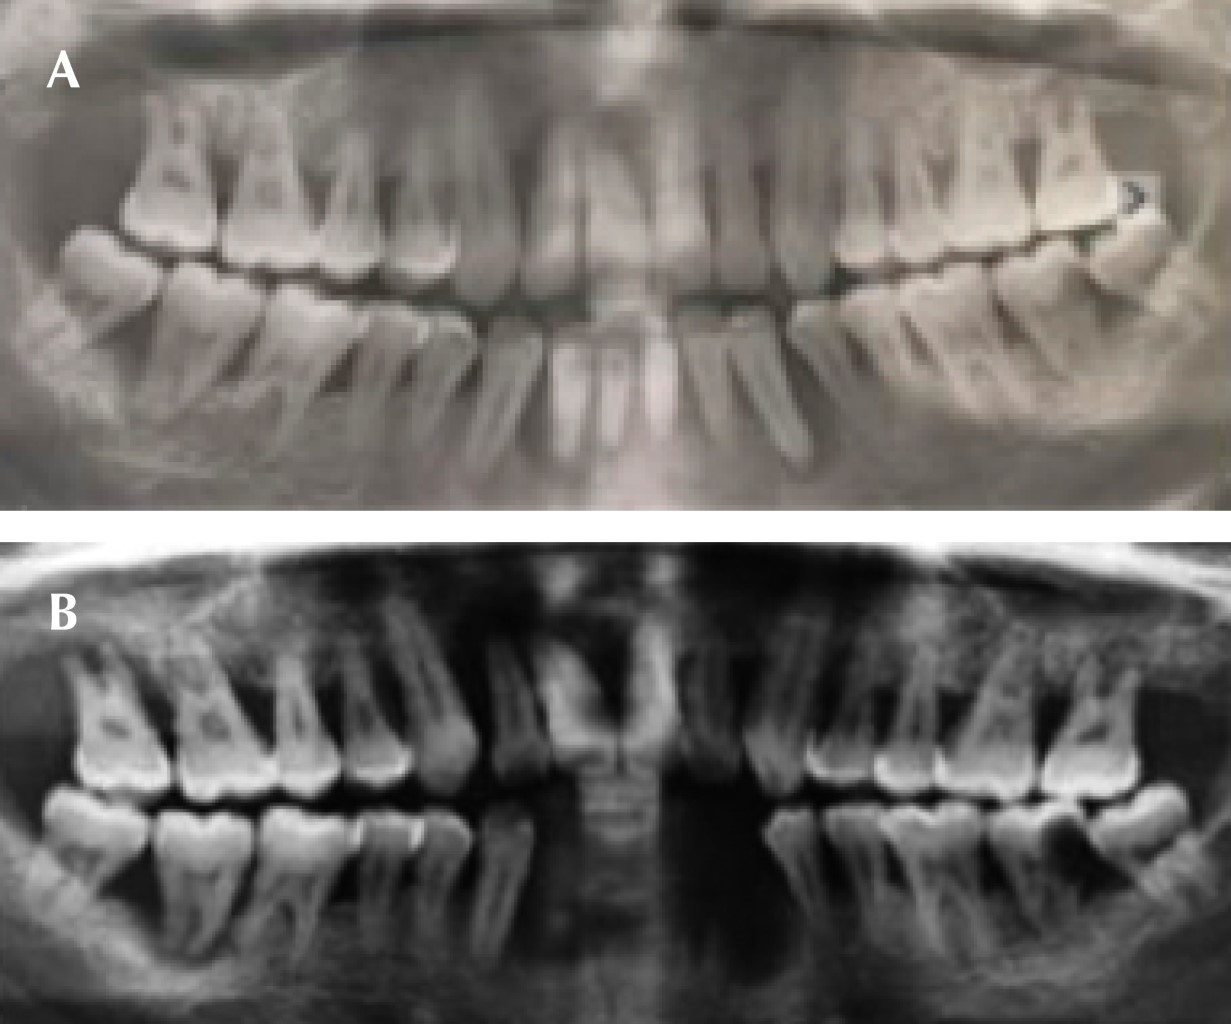

A la inspección clínica se observaron múltiples abscesos periodontales, presencia de placa microbiana (biofilm), cálculo supragingival y subgingival (Figura 5). Con base en estas características y después de haber identificado diversos factores de riesgo, se tomó glucemia por medio de una prueba capilar con valor de 172 mg/dL en ayuno. Con los elementos obtenidos se realizó el diagnóstico periodontal: periodontitis etapa III generalizada grado B (Figura 6).

Se inició la fase I y con base en la adherencia al tratamiento periodontal y un adecuado seguimiento, a pesar de la renuencia de iniciar un tratamiento sistémico se obtuvo una respuesta favorable. El paciente abandona el tratamiento por dos años, a su regreso afirmó que ya es diabético e hipertenso, sometido a tratamiento a través de metformina y enalapril respectivamente. Por medio de radiografías panorámicas y la inspección clínica se observó mayor pérdida ósea generalizada, lo cual mostró la progresión de la enfermedad periodontal, debido al desapego al tratamiento y la suma del factor sistémico (Figura 7A y B). Se inició (nuevamente) la fase I periodontal, realizando múltiples extracciones, debido a las condiciones en las que se presentó. Posteriormente se rehabilitó por medio de una prótesis parcial removible provisional inmediata (Figura 8A y B).